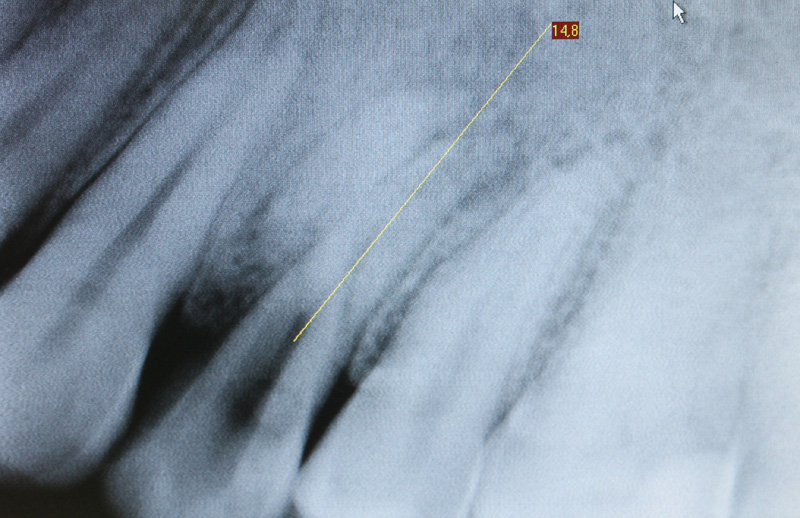

Sono mostrate le Rx prima e dopo l'intervento.